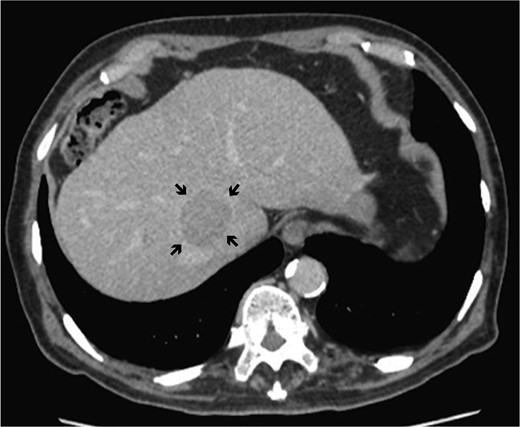

A 78-year-old man with a history of hepatitis C was referred to Keio University Hospital for a 4-cm HCC located between the roots of the middle hepatic vein (MHV) and right hepatic vein (RHV) (Fig. 1). The preoperative liver function test was nearly normal (Child-Pugh classification A, ICG retention rate 9.4%). Preoperative volumetry showed that caudate lobectomy with major hepatectomy exceeded the resection limits of the institution (functional remnant volume: 327 ml [31.6%]). His preoperative alpha-feto protein and carbohydrate 19–9 levels were 3.0 ng/ml and 18 U/ml, respectively.

Dynamic computed tomography of the liver. Portal phase of dynamic CT shows a low-density area abutting the RHV, indicating hepatocellular carcinoma located in the caudate lobe (arrows).